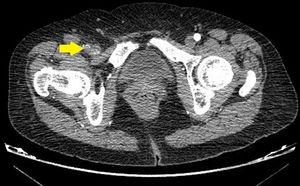

Given the suspicion of acute arterial ischemia, computed tomography angiogram (CT-angiogram) was performed (Figs. 1 and 2), which revealed obstruction of the right common FA with posterior recanalization; the superficial and deep FA were permeable, and another obstruction was found in the third portion of the popliteal artery and the origin of the tibioperoneal trunk.

With the finding of an occlusive thrombus in the lumen of the common FA, urgent surgery was indicated. Upon manual release of the artery, a mechanical obstacle was palpated in the iliofemoral transition that corresponded with the stitch of the hernia repair cone anchored to the adventitia of the vessel.

In our case, the suture trapped the adventitial layer on the anterior side of the artery, causing stenosis that led to secondary thrombosis of the common FA and a distal embolism. Postoperative analgesia and the slow progression of functional limitation disguised the symptoms of ischemia, delaying diagnosis for up to 3 days, which initially led to a neurological sequela despite optimal limb revascularization.